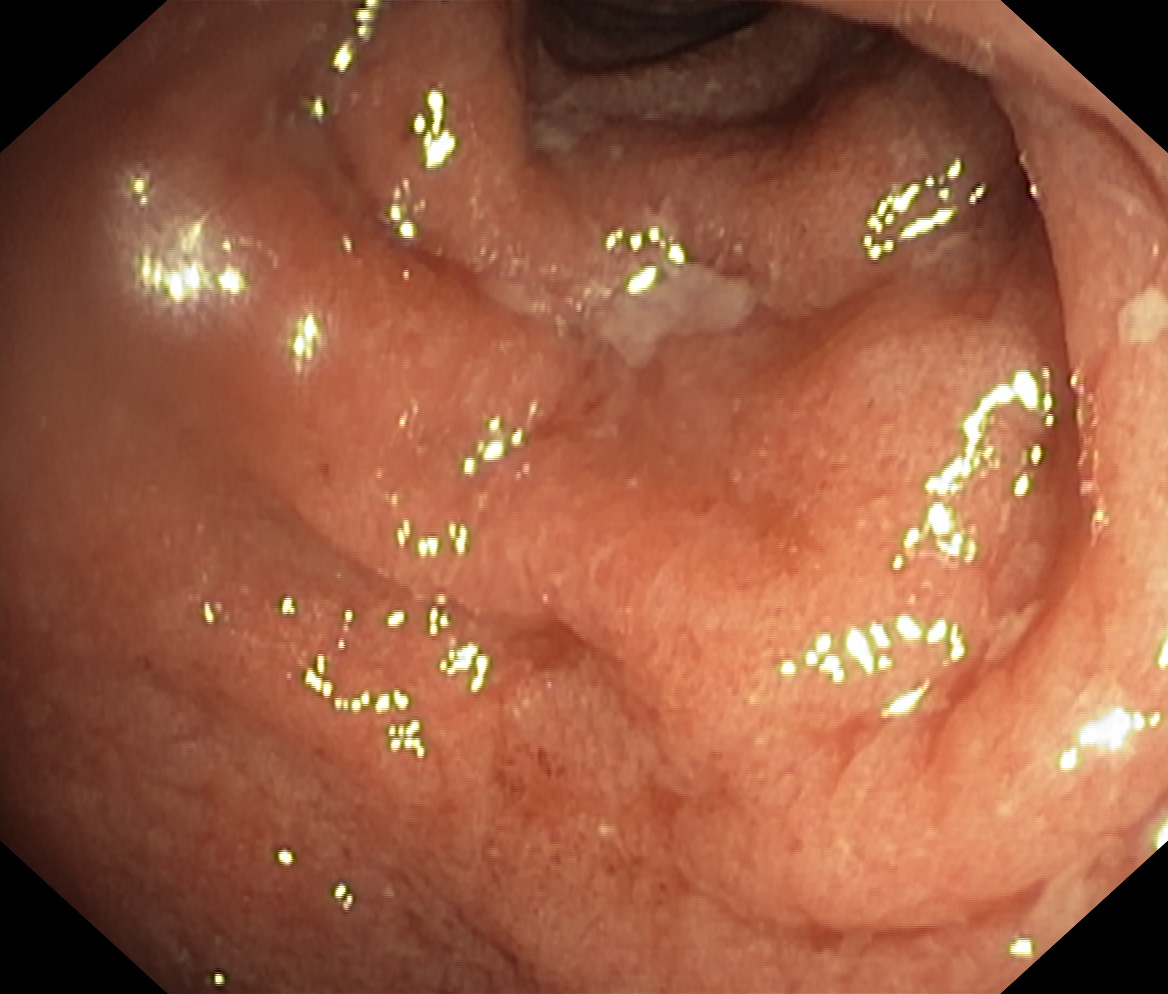

Zmiany łagodne

Polipy